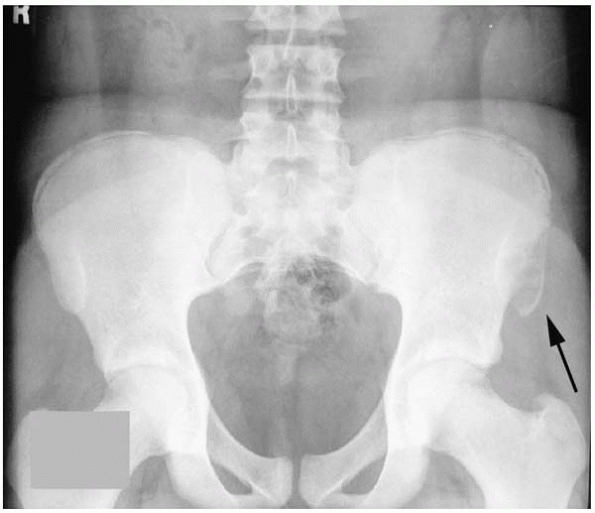

![]() |

|

▪ FIGURE 17-4 The pelvis is a notorious area for hiding tumors. (A) This AP radiograph shows a slight abnormality in the left iliac wing. (B) An MRI visualizes the extent of this malignancy.

▪ FIGURE 17-11 One key to making the diagnosis of Ewing sarcoma is the large soft-tissue mass. (A)

What is causing the destruction of the superior and inferior pubic ramus and ischium seen on this AP pelvis radiograph of an 11-year-old boy? (B) The MRI shows the huge soft-tissue mass associated with this Ewing sarcoma. |